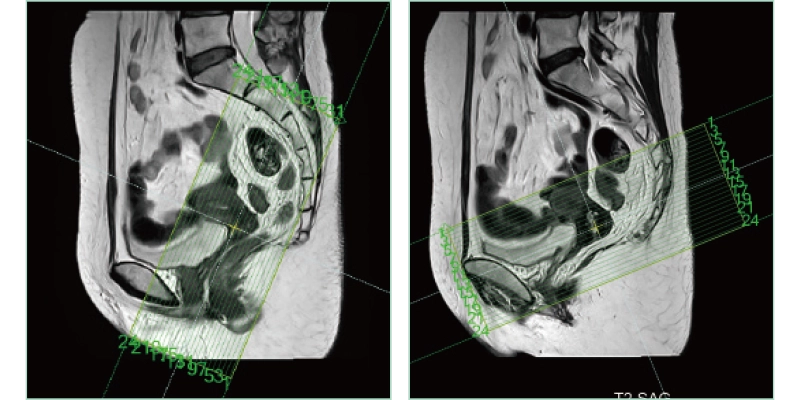

AutoPose FemalePelvis

The slice line setting support function, "AutoPose," automatically sets the slice lines as soon as the scanogram is scanned.